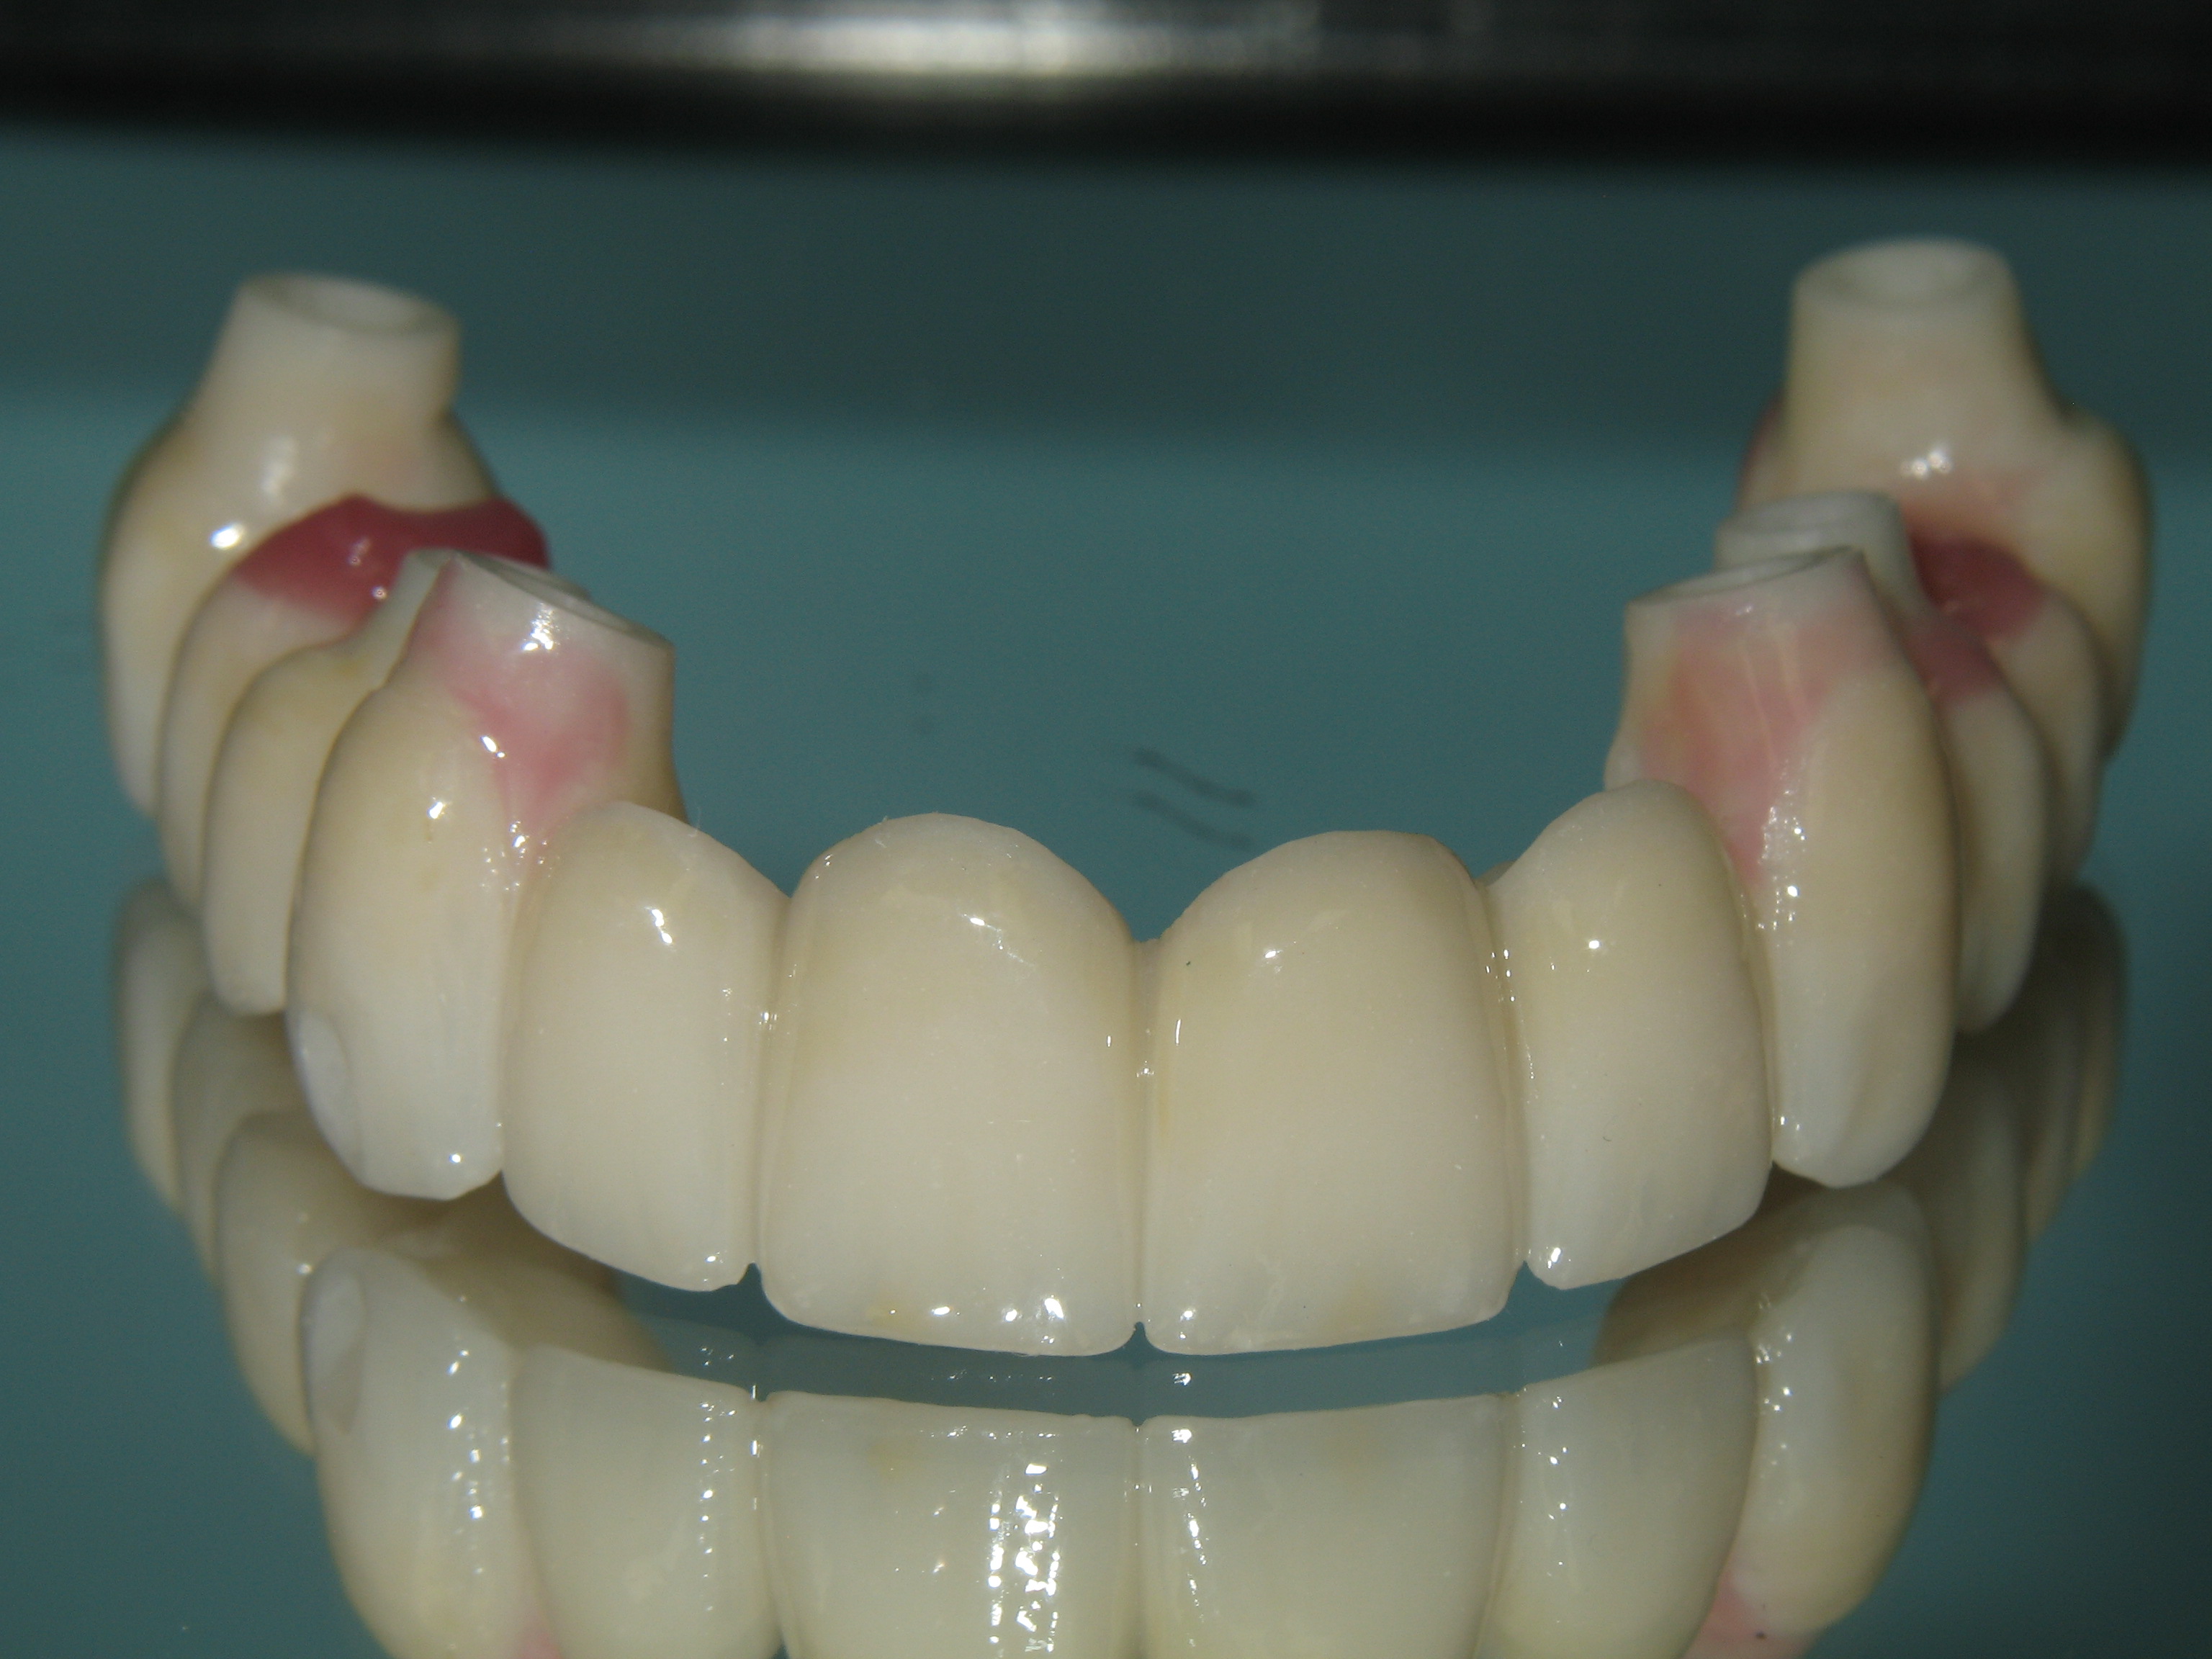

Although harder than other light-cured options, the zirconium silicate composite is more resilient and elastic than conventional ceramics. It also simulates the wear of enamel, favoring more natural attrition over catastrophic fractures. Repairs can be done directly in the mouth. Moreover, the material is very polishable, allowing ease of adjustments during delivery and occasional maintenance (Figure 10). In addition, the microstructure promotes a hygienic, plaque-resistant surface.

The material does not require firing, so coefficients of thermal expansion are not a concern. The material works with all varieties of frameworks; it has demonstrated years of success in veneering over CAD/CAM tooth form metal frameworks. Frameworks can be designed from scans of approved prototypes that are digitally cut back, allowing a complete wrapping of 1 to 2 mm of the microceramic (Figure 11).26

Fig 10. The zirconium silicate composite can be repaired in the mouth or returned to the lab to be refreshed, as in this case.

Figure 10